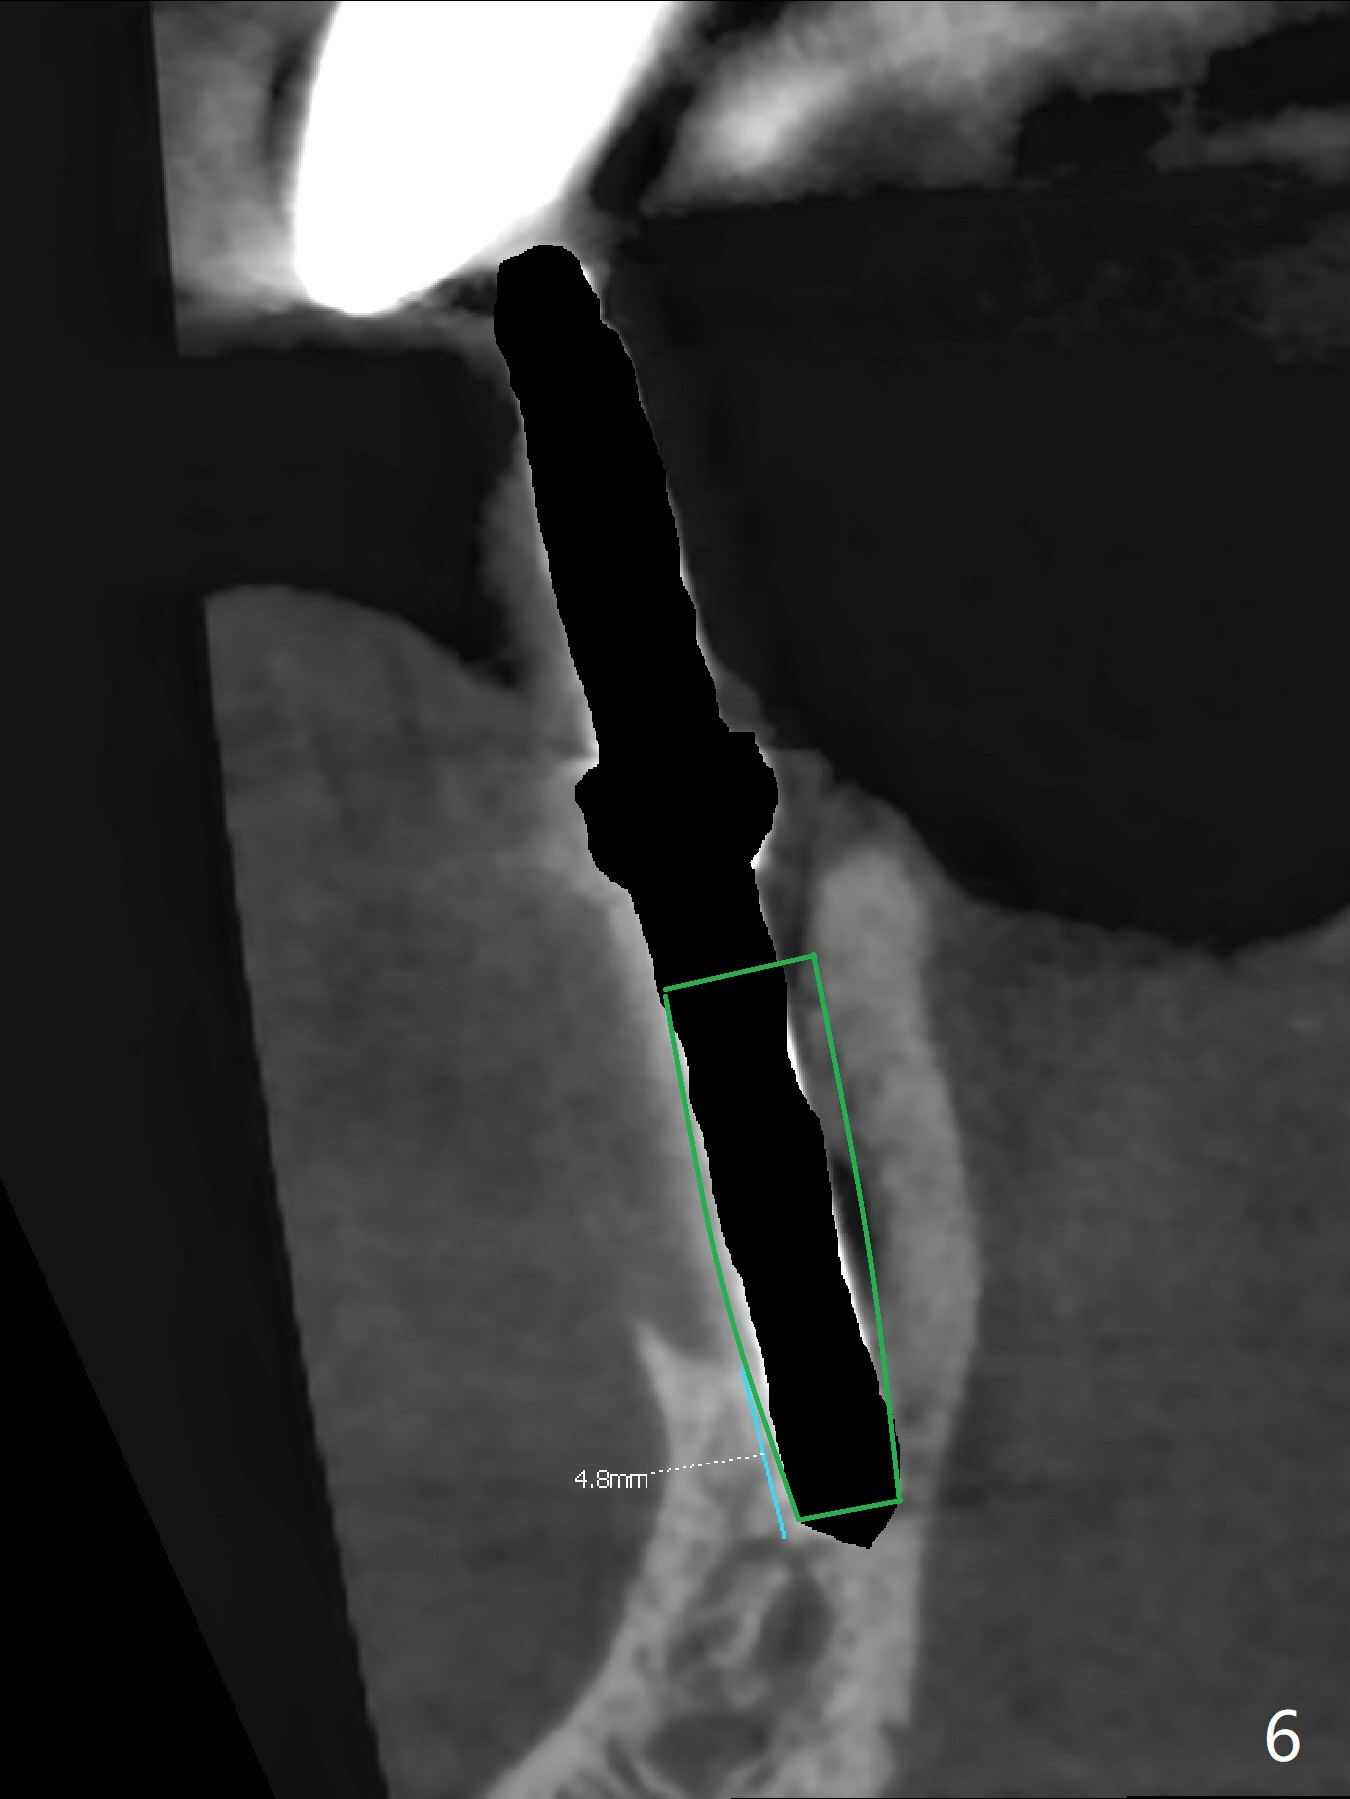

After removal of the split residual roots at #22 (Fig.1), the buccal wall is found to be defective, while the coronal portion of the lingual one (Fig.2 L) is confirmed to be more buccal than the apical portion. A vertical slot is made in the coronal portion of the lingual plate (Fig.3 *) in order to establish osteotomy lingual (Fig.4 O). The depth of the osteotomy in the apical native bone is 4.8 mm (Fig.5 CT coronal section). After the final drill (3 mm) is removed, a 3.8x16 mm implant is placed lingually for secure 2-pointed fixation (Fig.6,7, coronally: mesiolinguodistal; apically: in the native bone (Fig.9)). The essence of the lingual placement is the presence of a large buccal gap for Osteogen plug (Fig.8 yellow) and allograft (Fig.8 red, 9,10 (*)) for potential regeneration of the buccal plate. With bone graft and the overlying provisional (Fig.11 P), the buccal plate seems to have been established (*) 1 week postop. There is no obvious implant thread exposure 8 months postop (Fig.12). But the buccal plate is atrophic when the crown is cemented (~10 months postop, Fig.13).